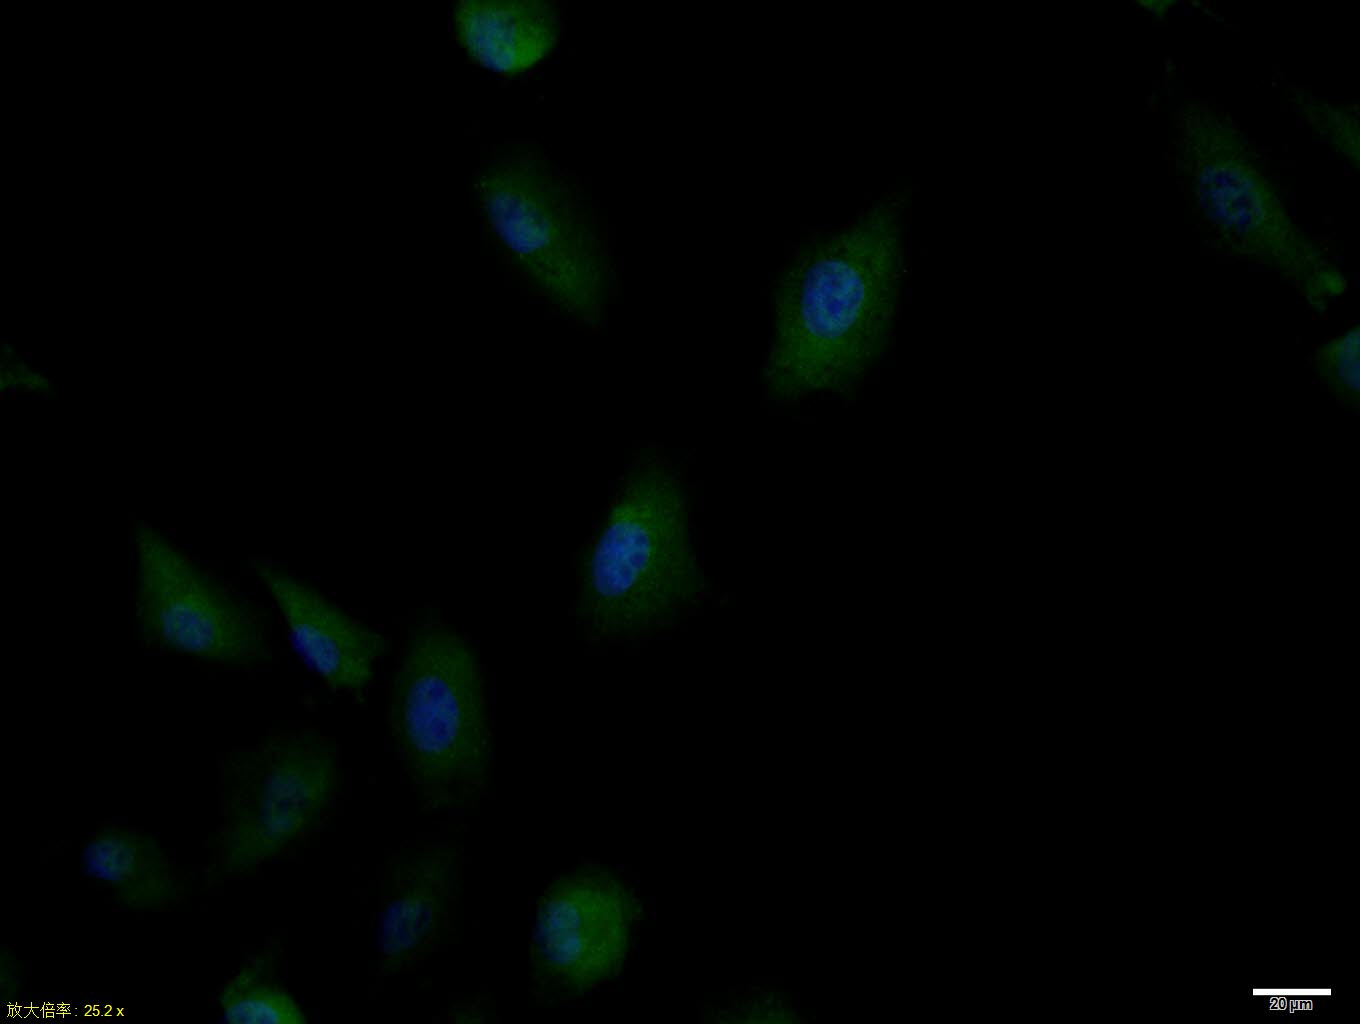

A549 cell; 4% Paraformaldehyde-fixed; Triton X-100 at room temperature for 20 min; Blocking buffer (normal goat serum, C-0005) at 37°C for 20 min; Antibody incubation with (phospho-IRS1 (Ser636 + Ser639)) polyclonal Antibody, Unconjugated (bs-3201R) 1:100, 90 minutes at 37°C; followed by a conjugated Goat Anti-Rabbit IgG antibody at 37°C for 90 minutes, DAPI (blue, C02-04002) was used to stain the cell nuclei.